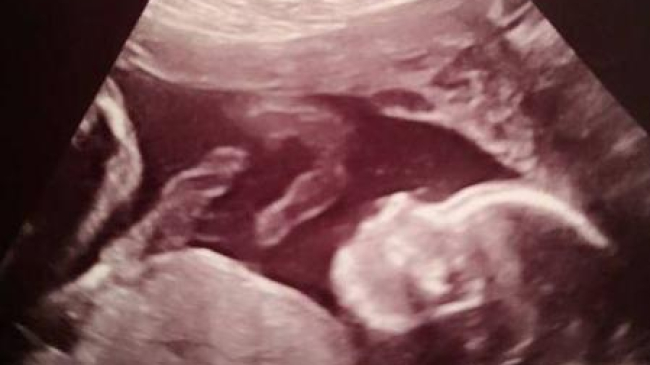

Pacientele au fost Bethan Simpson, o tânără de 26 de ani și fetița ei nenăscută. Potrivit ziarului The Mirror, doctorii au descoperit la analize, în cea de-a 20-a săptămână de sarcină, că micuța are spina bifidă, un defect de închidere de os la coloana vertebrală, care îi putea afecta capacitatea copilului de a merge.

„Și eu, și bebelușul am trecut prin teste de lichid amniotic, RMN și nenumărate ecografii”, a spus mama fetiței, potrivit The Mirror.